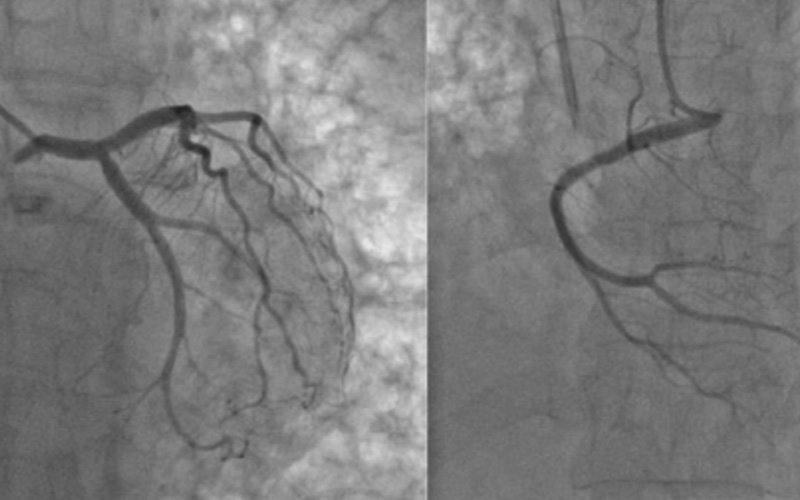

CORONARY ANGIOGRAM

A coronary angiogram is a special X-ray test. It’s done to find out if your coronary arteries are blocked or narrowed, where and by how much.